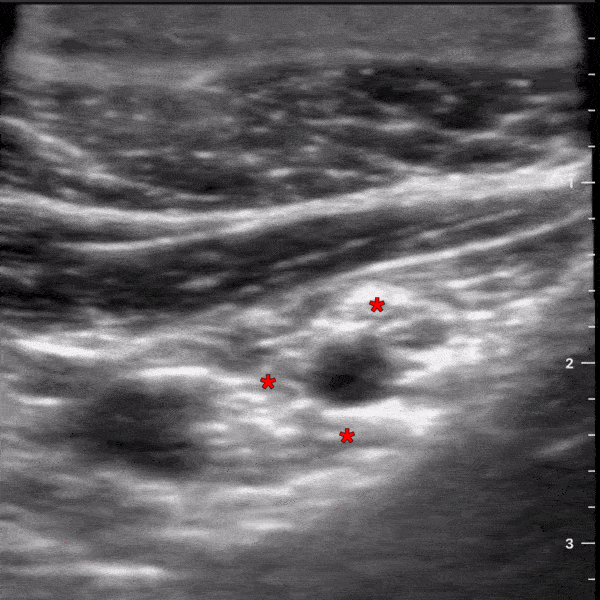

This is an ultrasound clip demonstrating the anatomy for an infraclavicular block. The probe is placed in a parasagittal orientation just medial to the coracoid process and inferior to the clavicle. The axillary artery can be seen pulsating in the middle of the screen. The * denotes the three cords of the the brachial plexus at this location (lateral, medial, and posterior). Two muscles layers can be seen at the top of the screen, pec major and the underlying pec minor. Michael Macias